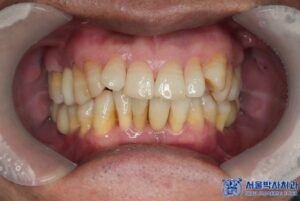

수술 후 약 3개월간의

치유기간을 거친 후,

최종 임플란트 보철물을

세팅해드렸습니다.

서울박사치과에는

원내 기공소가 있기 때문에

더욱 정밀하게 보철물을

제작할 수 있는데요.

특히 10년 이상의 경력을 가진

전문 기공사가 상주하고 있어

퀄리티 높은 보철물 제작이 가능합니다.

또한 맞춤형 지대주를 사용하여

음식물이 끼임이 적고

환자 구강 구조에 완벽히 맞춰

보철을 제작하고 있습니다.

내구성이 높은 재료를 사용하여

오래 사용할 수 있으며,

자연치아처럼 심미적인 면도 우수합니다.

환자분은 처음 내원하셨을 때

흡연자였고 잇몸 상태가

전반적으로 좋지 않았습니다.

하지만 저희가 내원하실 때마다 금연의 중요성을

강조드렸고 실제로 수술을 받으신 후로는

많이 자제하셔서 회복도 매우 잘 되셨고,

현재는 임플란트를 아주 잘 사용하고 계십니다.